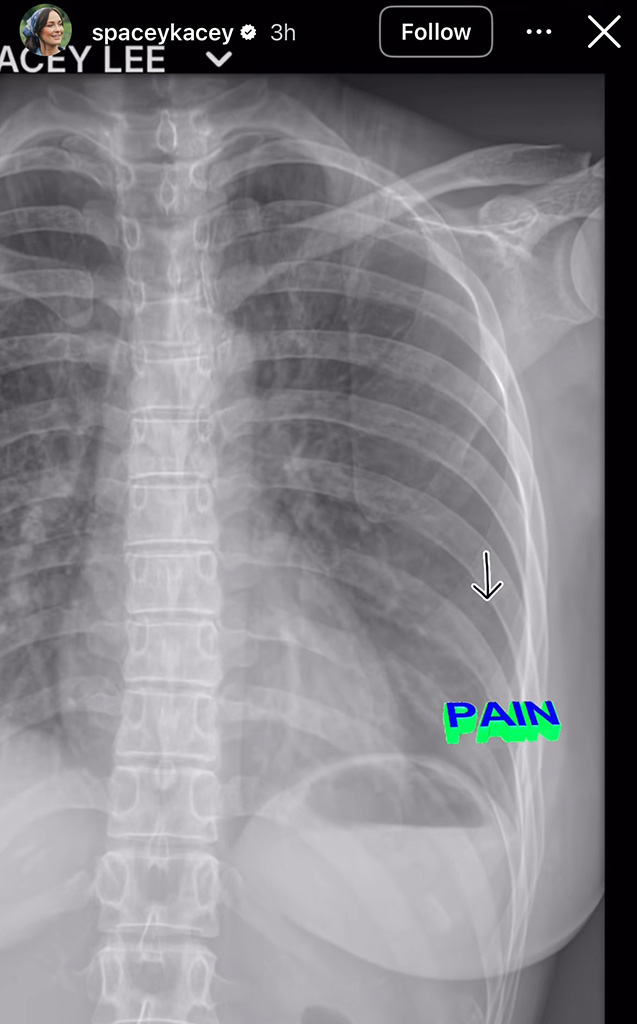

“Sooo I’m in Mexico with a f–king broken rib,” Kacey, 36, wrote on an image of her X-ray on her Instagram Story June 19. “Wednesday night it was raining and I was running to grab some towels and had an extremely hard fall on some very slick tile I didn’t see. Thankful I didn’t smack my head but I landed very very hard on my back left ribcage, and I broke rib number 6.”

Giving fans another close up of her injury, Kacey shared another X-ray of her torso with the word “pain” written over the section of her rib that is broken.